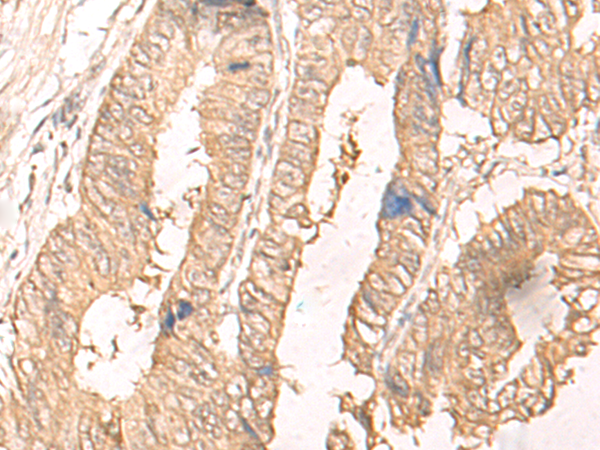

IHC positive control: |

Human cervical cancer and Human colorectal cancer |

IHC Recommend dilution: |

30-150 |